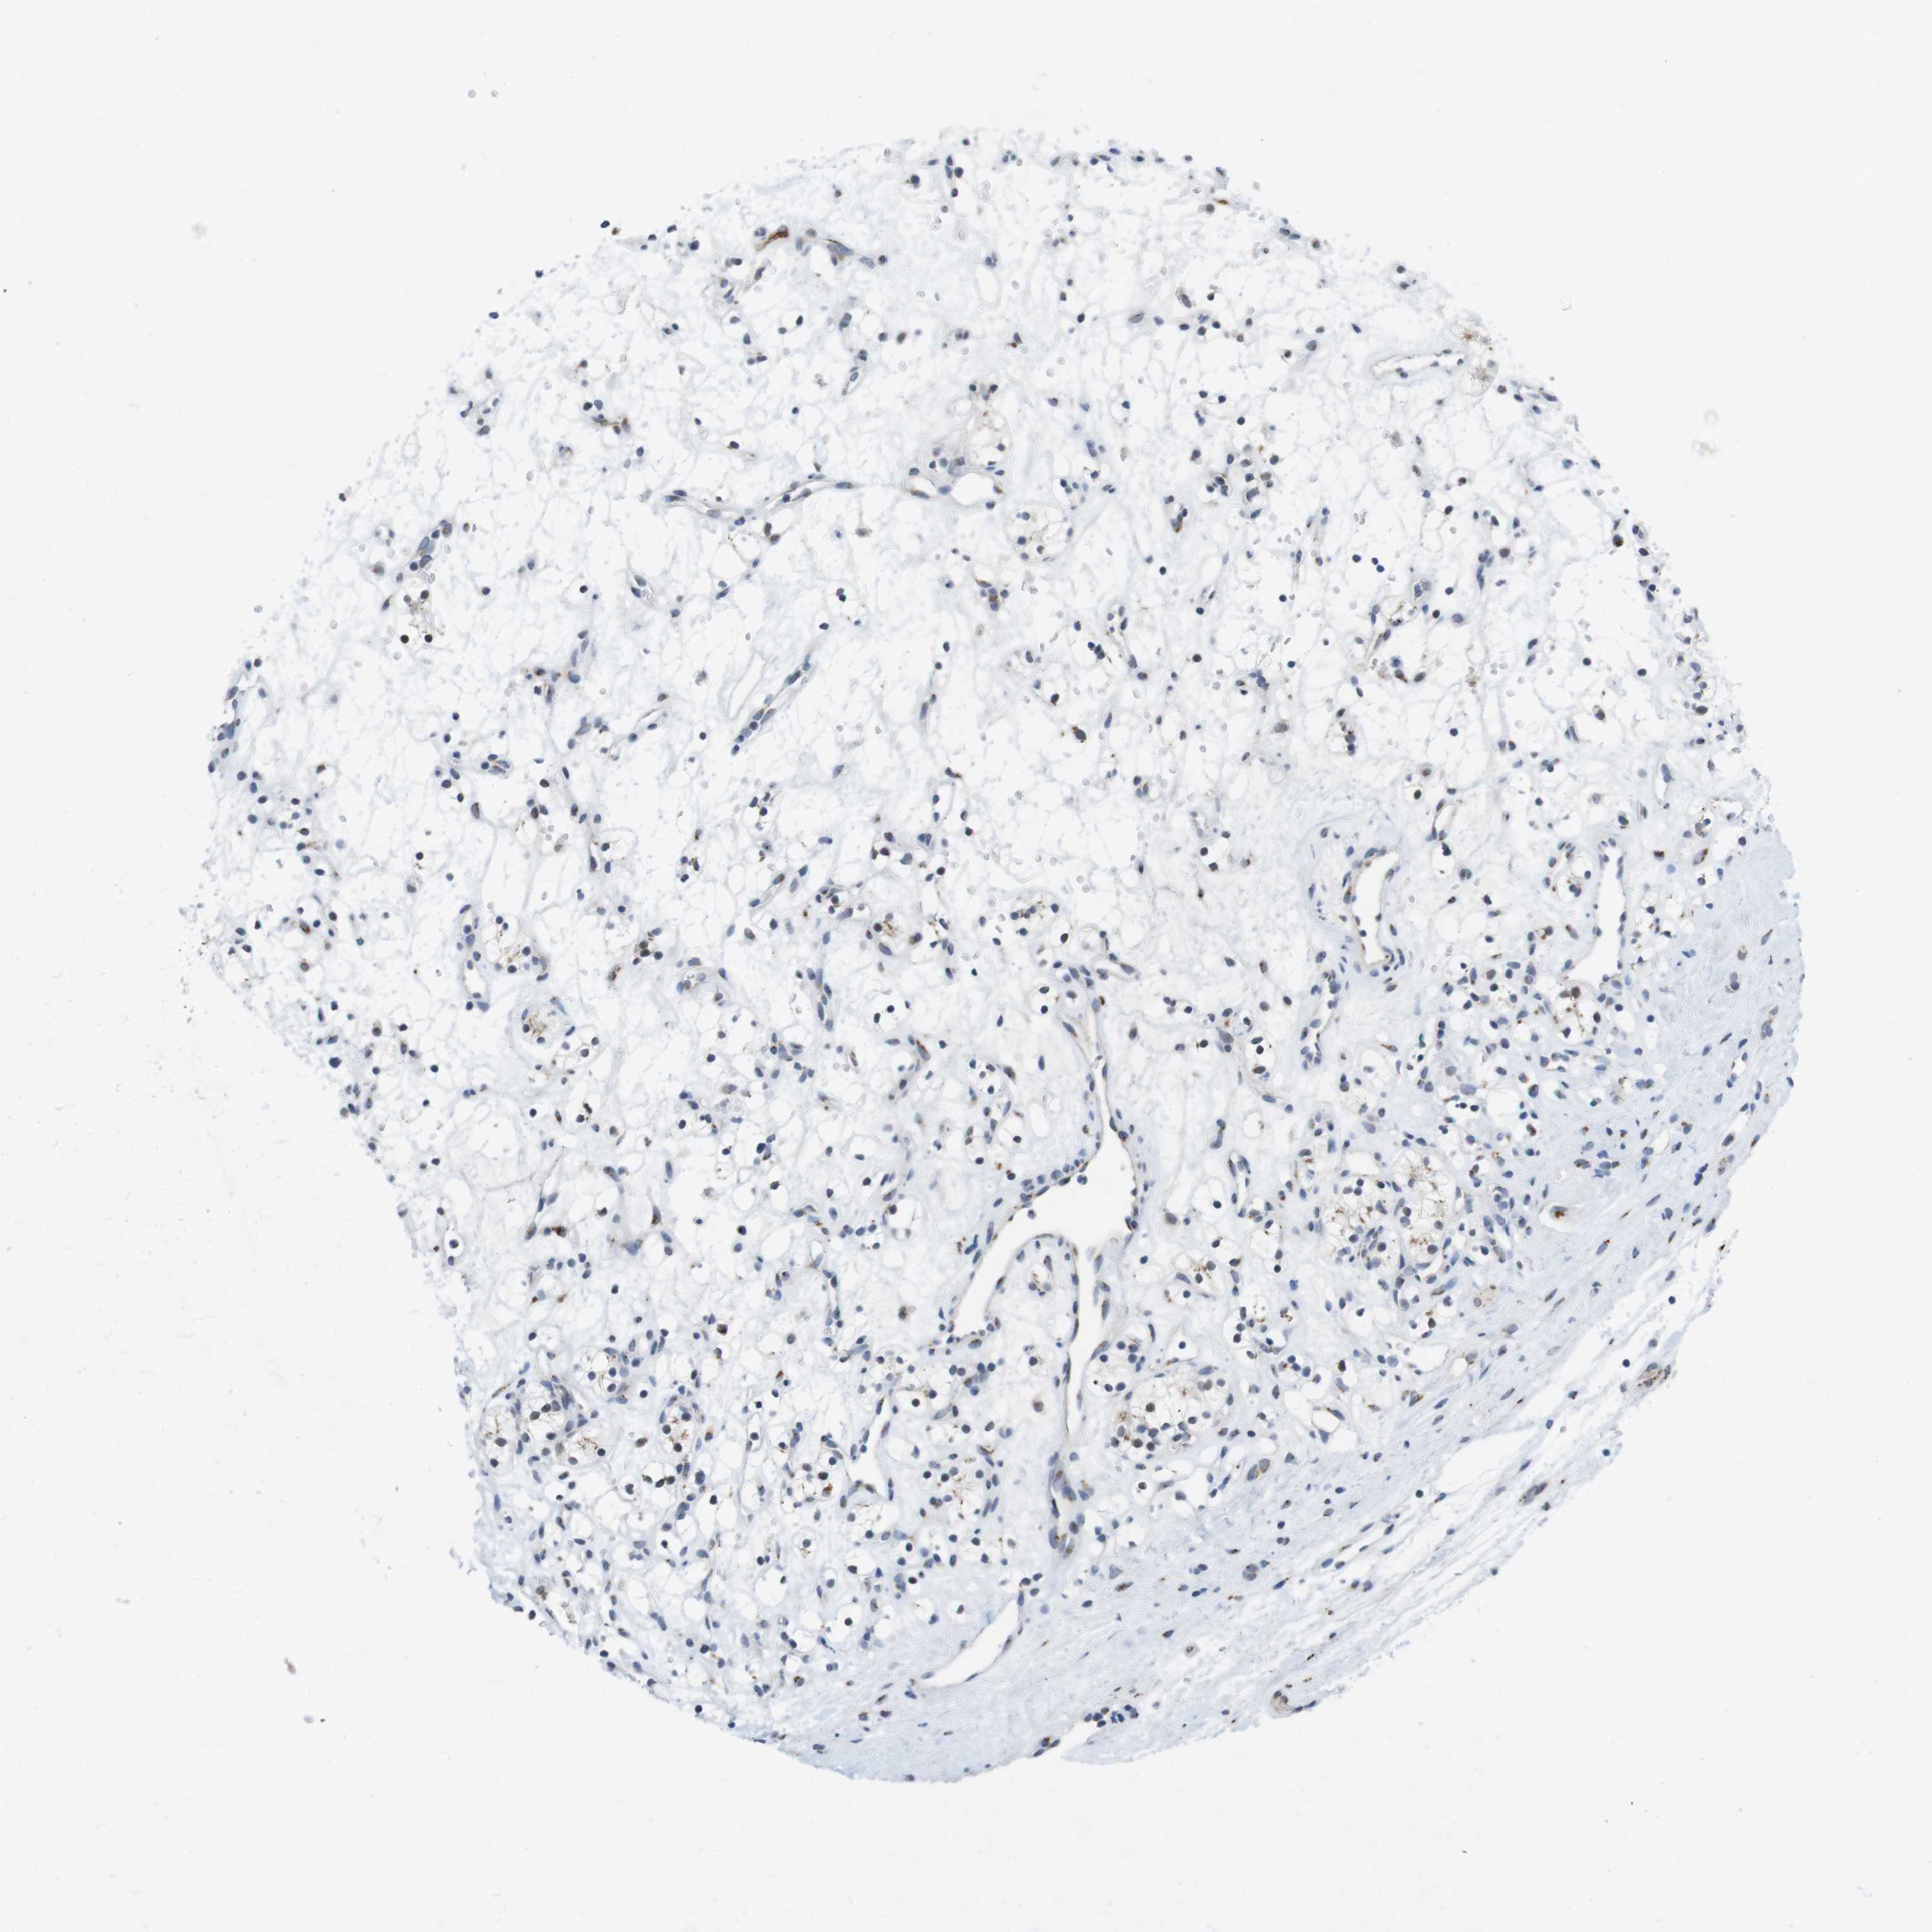

CANCER RENAL CANCER Show tissue menu

KICH TCGA KIRC TCGA KIRC VALIDATION KIRP TCGA PROTEIN RCC CPTAC PROTEIN EXPRESSION